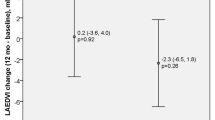

Recent study demonstrated that T1 and T2 mapping may distinguish myocardial involvement in CKD from the phenotypically similar presentations in hypertrophic cardiomyopathy (HCM) [41•]. Native T1 identified abnormal myocardium underlying the hypertrophic remodeling in both pathologies; however, native T2 values were increased only in the CKD-driven hypertrophic changes [41•]. The results of another study showed increased values of natives T1, reduction of LV volumes, and no change in LV mass and natives T2 values in patients 2 months after renal transplantation [42]. Slow improvement in cardiac function after renal transplantation, which was reported in several studies, is in line with previous findings that renal failure not only is a prognostic marker in HF but also triggers the HF progression.